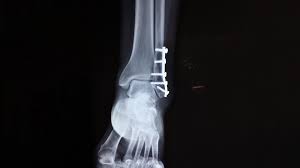

Sprunggelenkfraktur Wikiwand

Chronik Einer Sprunggelenkfraktur Sky Junkies